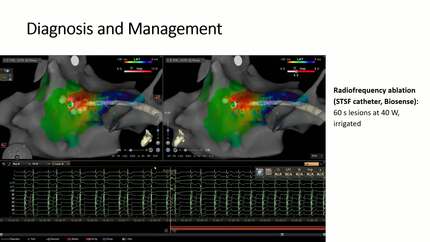

Management of a patient with high-burden parahisian ventricular ectopy and severe left ventricular impairment

Speaker: Doctor A. Hawley (Exeter, GB)